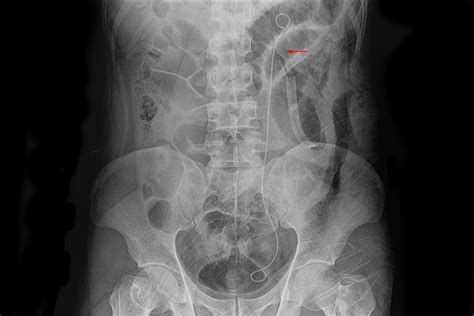

During the procedure, the urologist uses a cystoscope—a thin, lighted tube—inserted through the urethra into the bladder to locate the opening of the ureter. A guide wire is then passed through the ureter to the kidney. Once the position is confirmed via X-ray imaging, the stent is threaded over the wire and placed into the final position. The stent usually features small curls at both ends—one in the kidney and one in the bladder—to prevent it from migrating out of place.